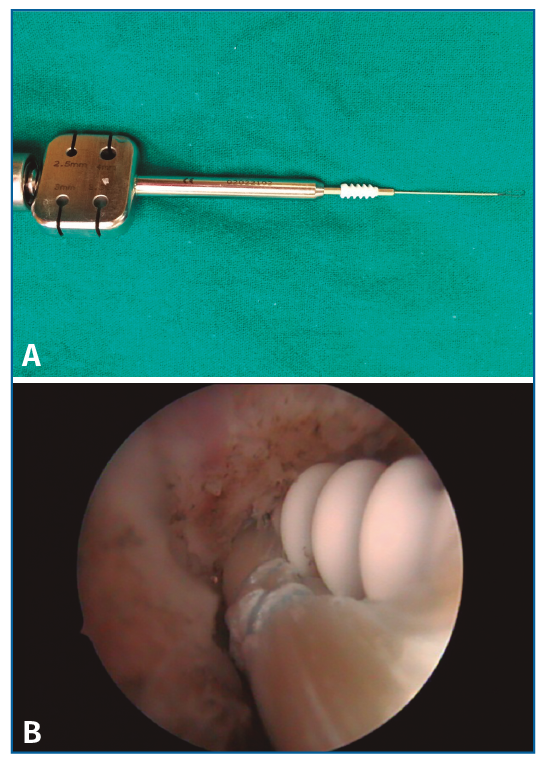

El material utilizado para esta técnica consta de: 2 tornillos de biotenodesis de 5 × 15 mm de Arthrex y artroscopio de 4,5 mm.

Con un alambre se realiza un stripping del mismo obteniéndolo fácilmente. El tendón obtenido tiene que tener un mínimo de 10 cm, lo que nos va a permitir doblar el tendón y obtener una plastia de 5 cm con el doble de grosor, unos 4-5 mm. Con una sutura realizamos un trenzado de 1,5 cm en cada extremo con el resto del hilo libre, que nos permitirá dar tensión a la misma cuando la coloquemos (Figura 4).

Figura 4. Plastia preparada de 5 cm de longitud.